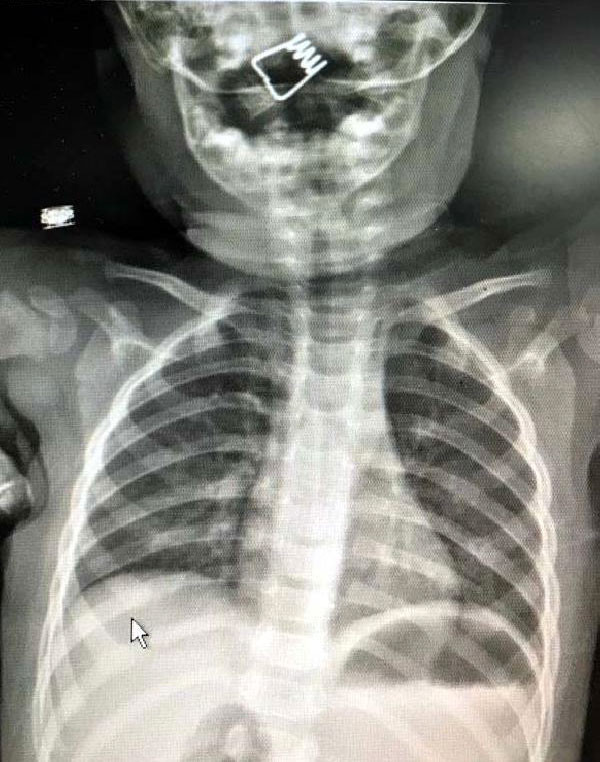

NEVŞEHİR'de inanılması güç bir olay yaşandı. 1 yaşındaki erkek bebek Ö.Y. önüne konulan çamaşır mandalıyla oynarken mandal dağıldı. Minik bebek de mandalın metal yayını hemen ağzına attı. Bebeğin ani tepki verip yutkunması sonrası metal yay, çocuğun boğazına kaçtı. Hastanede çekilen röntgende yayın yeri tespit edildi. Bebeğin nefes borusuna saplanan yay başarılı bir operasyonla çıkarıldı.

Nevşehir Devlet Hastanesi Acil Polikliniği'ne getirilen bebeği, Acil Nöbetçi doktoru Mustafa Alpaslan muayene ederek gerekli tetkikleri yaptı. Çekilen röntgen filmlerinde mandal yayının lokalizasyonu ve durumu belirlendi. Daha sonra, KBB Uzmanı Op. Dr. Ahmet Cevatzade tarafından yapılan başarılı ameliyat sonucunda bebeğin genzine saplanan mandal yayı çıkartıldı.